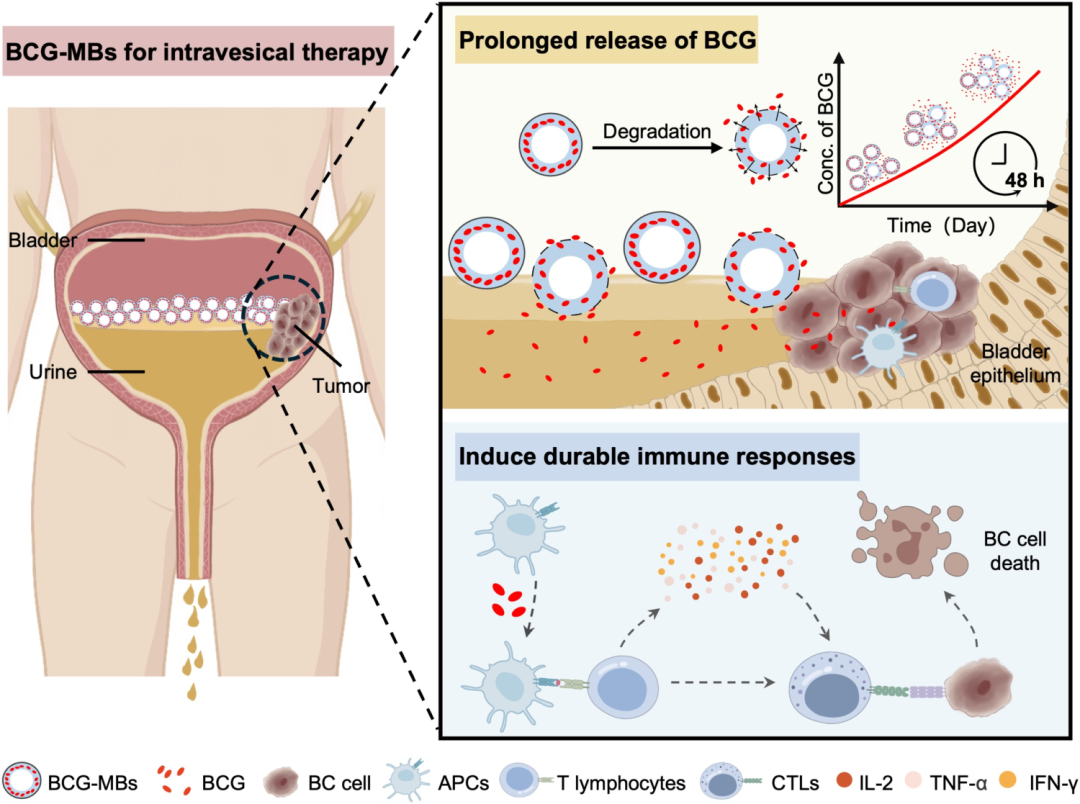

本研究聚焦于解决膀胱癌免疫治疗中的关键瓶颈问题——卡介苗(BCG)在膀胱内滞留时间过短的挑战。研究团队创新性地开发了一种基于浮动空气微气泡的药物递送系统(BCG-MBs),通过将BCG封装在特制的微气泡中,使其能够稳定漂浮在尿液表面而不随排尿被迅速排出,从而实现BCG在膀胱内的长期滞留和持续释放。这种微气泡系统采用乳化、交联和冷冻干燥的策略制备,形成具有三层结构(内层空气核心、中间溶液层和外层壳)的微球,其平均尺寸为102微米,内部空气核心直径约85微米,平均密度仅为509.82 kg/m³,远低于尿液密度,确保了其在膀胱内的漂浮特性。这一设计巧妙利用了物理浮力原理,避免了传统粘附性水凝胶可能干扰膀胱正常生理功能的缺陷,也无需依赖复杂的外部磁场设备。

图 BCG-MBs用于膀胱癌(BC)膀胱内免疫治疗的应用示意图

在实验验证过程中,研究团队通过多种技术手段全面评估了BCG-MBs的性能。体外实验表明,BCG-MBs在尿液中表现出优异的漂浮能力,24小时后仍有超过50%的微气泡保持漂浮状态;而在模拟排尿的条件下,BCG-MBs能够持续释放BCG,维持治疗有效浓度达24小时以上。更为重要的是,在原位膀胱癌SD大鼠模型中,与传统BCG治疗相比,BCG-MBs治疗组展现出显著增强的治疗效果:不仅肿瘤生长受到更有效的抑制,还诱导了更持久的免疫反应,表现为IL-2等关键细胞因子水平的持续升高,同时未观察到明显的系统毒性。这些结果充分证明,通过延长BCG在膀胱内的作用时间,可以显著提升免疫治疗的疗效。

这项研究的创新之处在于巧妙利用微气泡的物理特性解决了临床治疗中的实际问题,为膀胱癌免疫治疗提供了新思路。BCG-MBs系统不仅实现了BCG在膀胱内的长期滞留和持续释放,还保持了BCG的生物活性,通过诱导更持久的TH1型免疫反应显著提升了抗肿瘤效果。值得注意的是,该平台技术具有良好的拓展性,不仅可以用于BCG的递送,还能够封装多种治疗剂,如化疗药物、免疫调节核酸或工程化外泌体,为膀胱癌的联合治疗提供了可能。此外通过功能化设计,该系统还可发展为智能响应型药物递送系统,进一步拓展至其他管腔器官疾病的治疗领域,展现出广阔的应用前景。